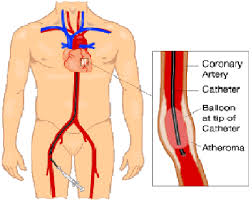

Overview

Package includes:

Days in hospital : 3 to 4 Days (For patient and one attendant)

Days in hotel : 7 Days (For patient and one attendant)

Room type in hospital : Shared

Room type in hotel : Private

Hotel category: Standard

Value added benefits of the Coronary Angioplasty:

Ø Doctor consultation charges

Ø Lab tests and diagnostic charges

Ø Room charges inside hospital during the procedure

Ø Surgeon Fee

Ø Nursing charges

Ø Hospital surgery suite charges

Ø Anesthesia charges

Ø Routine medicines and routine consumables (bandages, dressings etc.)

Ø Food and Beverages inside hospital stay for patient and one attendant.

Overview

Package includes:

Days in hospital : 3 to 4 Days (For patient and one attendant)

Days in hotel : 7 Days (For patient and one attendant)

Room type in hospital : Shared

Room type in hotel : Private

Hotel category: Standard

Value added benefits of the Angioplasty PTCA :

Ø Doctor consultation charges

Ø Lab tests and diagnostic charges

Ø Room charges inside hospital during the procedure

Ø Surgeon Fee

Ø Nursing charges

Ø Hospital surgery suite charges

Ø Anesthesia charges

Ø Routine medicines and routine consumables (bandages, dressings etc.)

Ø Food and Beverages inside hospital stay for patient and one attendant.

Overview

Package includes:

Days in hospital : 2 to 3 Days (For patient and one attendant)

Days in hotel : 14 Days (For patient and one attendant)

Room type in hospital : Shared

Room type in hotel : Private

Hotel category: Standard

Value added benefits of the Percutaneous transluminal coronary angioplasty (PTCA):

Ø Doctor consultation charges

Ø Lab tests and diagnostic charges

Ø Room charges inside hospital during the procedure

Ø Surgeon Fee

Ø Nursing charges

Ø Hospital surgery suite charges

Ø Anesthesia charges

Ø Routine medicines and routine consumables (bandages, dressings etc.)

Ø Food and Beverages inside hospital stay for patient and one attendant.